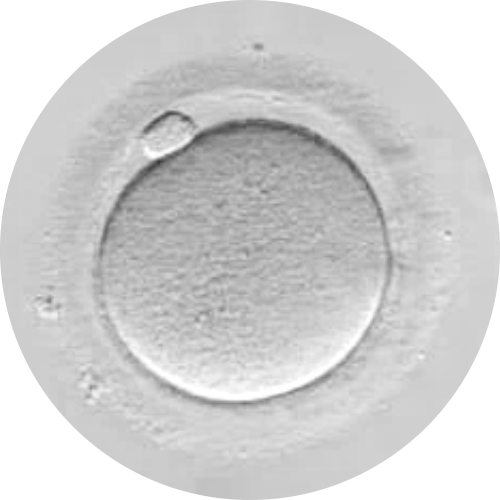

Oocytes are not only carriers of half the essential genetic material for creating life but also play a key role in early embryonic development. Their cytoplasm, rich in nutrients and metabolic factors, determines embryo viability and the success of conception.

- Oocyte Metabolic Assessment: Each egg undergoes metabolic and mitochondrial evaluation to identify energy deficits.

- Personalized Cytoplasmic Restoration: Infusion of energy and mitochondrial factors revitalizes the egg. Donor cytoplasm may be used when necessary without altering the patient’s DNA.